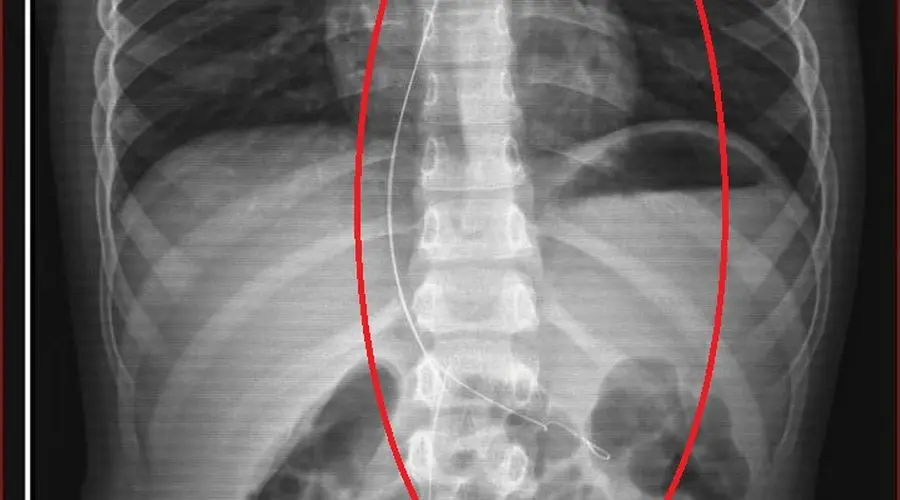

Şırnak’ta yaşayan 6 yaşındaki Aram Devran Ötün’ün vücudunda tam 3 yıldır unutulmuş 18 santimlik kateter olduğu ortaya çıktı. Ailesiyle piknik yaparken salatalık parçası yutan küçük çocuk, öksürük ve kusma şikayetleriyle hastaneye götürüldüğünde gerçeği öğrendi. Riskli ameliyat sonrası kateter çıkarılırken, ihmale ilişkin hem dava hem de soruşturma başlatıldı.

Mayıs ayında rahatsızlanan Aram, Şırnak Devlet Hastanesi’ne götürüldü. Çekilen röntgen ve MR’da vücudunda bir tıbbi malzeme tespit edilince küçük çocuk Diyarbakır’daki Gazi Yaşargil Eğitim ve Araştırma Hastanesi’ne sevk edildi. 5,5 saat süren zorlu bir operasyonla Aram’ın damar yolunda unutulan 18 santimetrelik kateter çıkarıldı. Kateterin, kalp kapakçığı ve akciğerlerde hasara yol açtığı belirlendi.

Ailenin avukatı Ahmet Yalçın, hastane hakkında hem şikayetçi olduklarını hem de dava açtıklarını belirterek, “Müvekkilim Aram Devran Ötün, 2022 Eylül ayında Dicle Üniversitesi Hastanesi’nde Stevens- Johnson hastalığı nedeniyle tedavi gördü. Tedavi sırasında kendisine kateter takıldı. 18 santimetre uzunluğundadır. Bunu takarken büyük bir ihmalkarlık yapılarak vücudunda unutuldu. Mayıs ayında müvekkilim çok öksürdüğü için Şırnak Devlet Hastanesi’ne kaldırıldı. Burada yapılan tetkiklerde kateterin unutulduğu tespit edildi. Daha sonra Diyarbakır Gazi Yaşargil Kadın ve Çocuk Hastalıkları Hastanesi’ne götürüldü. Çok riskli bir ameliyata alındı ve kateter çıkarıldı. Bu kateterin vücutta yol aldığı tespit edildi. İlk giriş yeri ve çıkarıldığı yer arasında çok fark var ve kalp kapakçığı ile ciğerlerine zarar verdiği tespit edildi. Müvekkillerimin hem maddi hem de manevi zararlarını karşılamak adına Dicle Üniversitesi’ne biz başvuruda bulunduk. 30 günlük cevap süresi içerisinde bize geri dönüş yapılmadı. Biz de maddi ve manevi zararların tazminat için Diyarbakır İdare Mahkemesi’ne davamızı açtık ve sorumlulardan şikayetçi olduk” dedi.

Oğlunun piknikte salatalık parçası yuttuktan sonra sürekli öksürmeye ve kusmaya başladığını söyleyen Semra Ötün, “Çocuğum 3 yıl önce Steven Johnson sendromu hastalığına yakalandı. Milyonda bir görülen antibiyotikten kaynaklı bir hastalık. Doktorlar öyle söyledi. Bizi acilen Diyarbakır Dicle Üniversitesi Çocuk Hastanesi bölümüne sevk ettiler. 1 ay yoğun bakım sürecimiz oldu. 28 gün yoğun bakımda, 3 günde serviste kaldı. Damar yolundan, kasıktan serum taktılar. Kateter denilen tel çocuğun vücudunda bırakılıyor. Biz taburcu olduğumuzda fark edilmiyor. 3 yılın sonunda biz bunu fark ettik. Pikniğe gittik. Oğlum salatalık parçası yuttu ve salatalık parçasından sonra akşama kadar öksürdü. Hiçbir şekilde durmadı. Kusuyordu. Ben şüphelenmeye başladım. Çocuğum normal değildi. Sonra eşime danıştım. Akşam 21.00 civarında acile götürdük. Röntgeni ve MR’ı çekildi. Tuhaf bir şey olduğunu anladık. Doktor röntgeni gösterdi. Tel kalmıştı. Çok kötü bir şekilde. Acil doktoru film çektikten sonra bize bir tel parçasını gösterdi. Bizi bekletmeden Diyarbakır’a sevkimizi verdiler. Diyarbakır Gazi Yaşargil Eğitim ve Araştırma Hastanesi Kadın Doğum ve Çocuk Ek Binası’na gittik. Çocuğun kasıklarından anjiyo yolu ile teli çıkaracaklarını ama riskli bir ameliyat olduğunu söylediler. O süreçte çocuk gerçekten sürekli yoruluyordu. İkide bir oturuyordu. ‘Anne çok yoruldum, karnım ağrıyor’ diyordu. Ben ağrı kesiciler ile geçiştirmeye çalışıyordum. Bu telin 3 yıl boyunca çocuğumda kaldığını öğrendim.” diye konuştu.